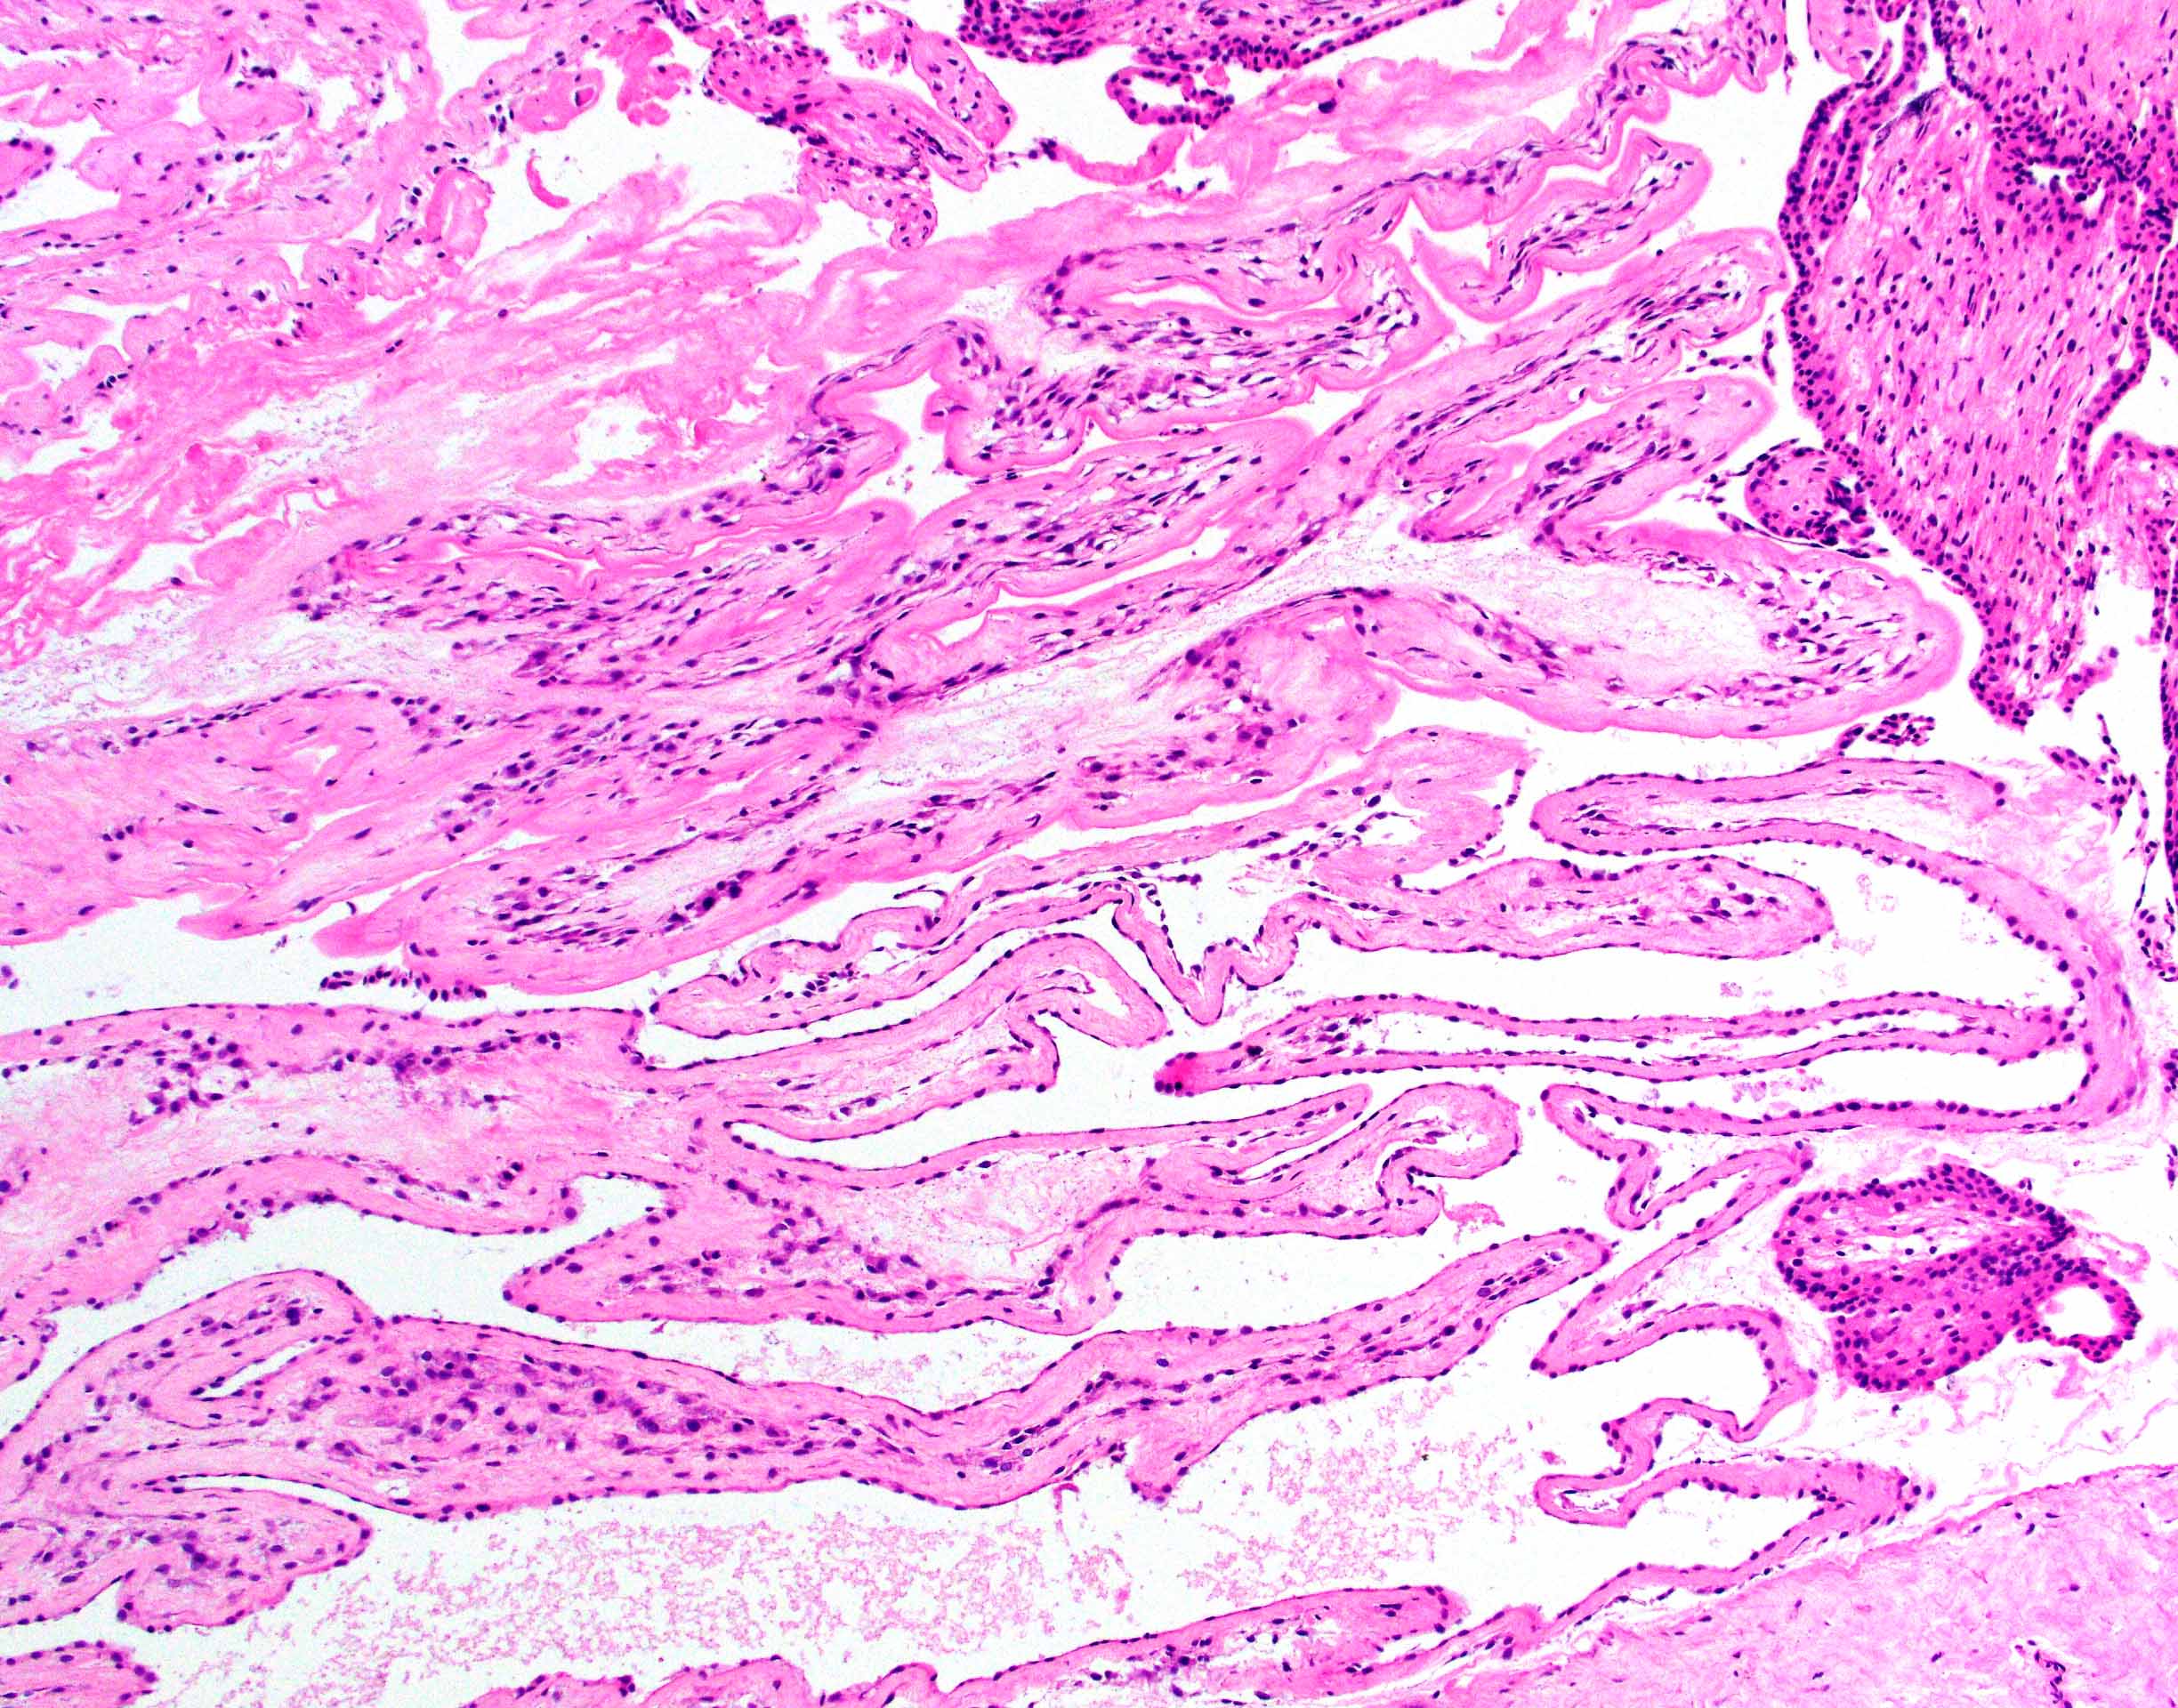

Microscopic (histologic) description

- Removed or passed products of conception may contain:

- Early first trimester chorionic sac (< 8 weeks): thin chorion and scant villi that are sparsely or nonvascularized

- Villous trophoblast is bilayered (mononuclear cytotrophoblast inner layer and multinucleated syncytiotrophoblast outer later) and circumferential with occasional polarized trophoblast protrusions

- Mid first trimester chorionic sac (8 - 10 weeks): may exhibit recognizable amnion, early stromal collagenization of chorion and proximal villi and increased volume of distal villi with distinct capillaries

- Later first trimester chorionic sac (> 10 weeks): may exhibit loose fusion of amnion and chorion, a more collagenized chorion and stem villi, more distinct walls of fetal vessels and numerous villi with increasing demarcation between proximal and distal branches

- Spectrum of villous changes in immature chorionic villi following embryonic death (Placenta 2005;26:114):

- Cellular debris within villous vessels - earliest change

- Villous edema with myxoid stromal degeneration - may be confused with molar gestation

- Collagenized avascular villi (villous sclerosis / fibrosis)

- Villous edema and sclerosis / fibrosis often coexist

- Other findings: prominent perivillous fibrin with prolonged retention or in medical abortions, otherwise pathologic

Microscopic (histologic) images

Contributed by Chrystalle Katte Carreon, M.D. and Drucilla J. Roberts, M.D.